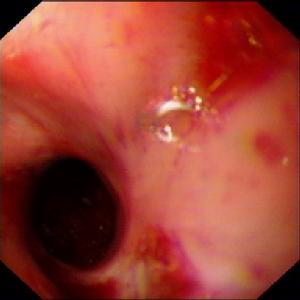

異物性食管穿孔手術圖2.穿孔部位 異物常易於在食管第一狹窄處卡住,故頸段食管穿孔者多見多數病例為口含或咀嚼時不慎滑入下咽部而進入食管有時則為幼兒無知誤吞。異物亦可在胸段第二狹窄的主動脈弓水平停留造成食管穿孔,亦可發生在阻塞性食管病變的上方部位。

2.內鏡檢查 除非X線檢查及對比劑檢查為陰性臨床高度懷疑食管穿孔者,很少需要做內鏡檢查內鏡亦可用於治療目的取出吞入異物。穿孔部已造成食管周圍膿腫者可行管腔內引流,達到治療目的。